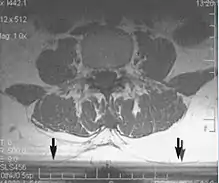

Metal artifacts

Metal artifacts occur at interfaces of tissues with different magnetic susceptibilities, which cause local magnetic fields to distort the external magnetic field. This distortion changes the precession frequency in the tissue leading to spatial mismapping of information. The degree of distortion depends on the type of metal (stainless steel having a greater distorting effect than titanium alloy), the type of interface (most striking effect at soft tissue-metal interfaces), pulse sequence and imaging parameters. Metal artifacts are caused by external ferromagnetics such as cobalt containing make-up, internal ferromagnetics such as surgical clips, spinal hardware and other orthopaedic devices, and in some cases, metallic objects swallowed by people with pica.[3] Manifestation of these artifacts is variable, including total signal loss, peripheral high signal and image distortion (Figs 3 and 4).[1] Reduction of these artifacts can be attempted by orientating the long axis of an implant or device parallel to the long axis of the external magnetic field, possible with mobile extremity imaging and an open magnet. Further methods used are choosing the appropriate frequency encoding direction, since metal artifacts are most pronounced in this direction, using smaller voxel sizes, fast imaging sequences, increased readout bandwidth and avoiding gradient-echo imaging when metal is present. A technique called MARS (metal artifact reduction sequence) applies an additional gradient, along the slice select gradient at the time the frequency encoding gradient is applied. ==Signal processing dependent artifacts== The ways in which the data are sampled, processed and mapped out on the image matrix manifest these artifacts.[1]